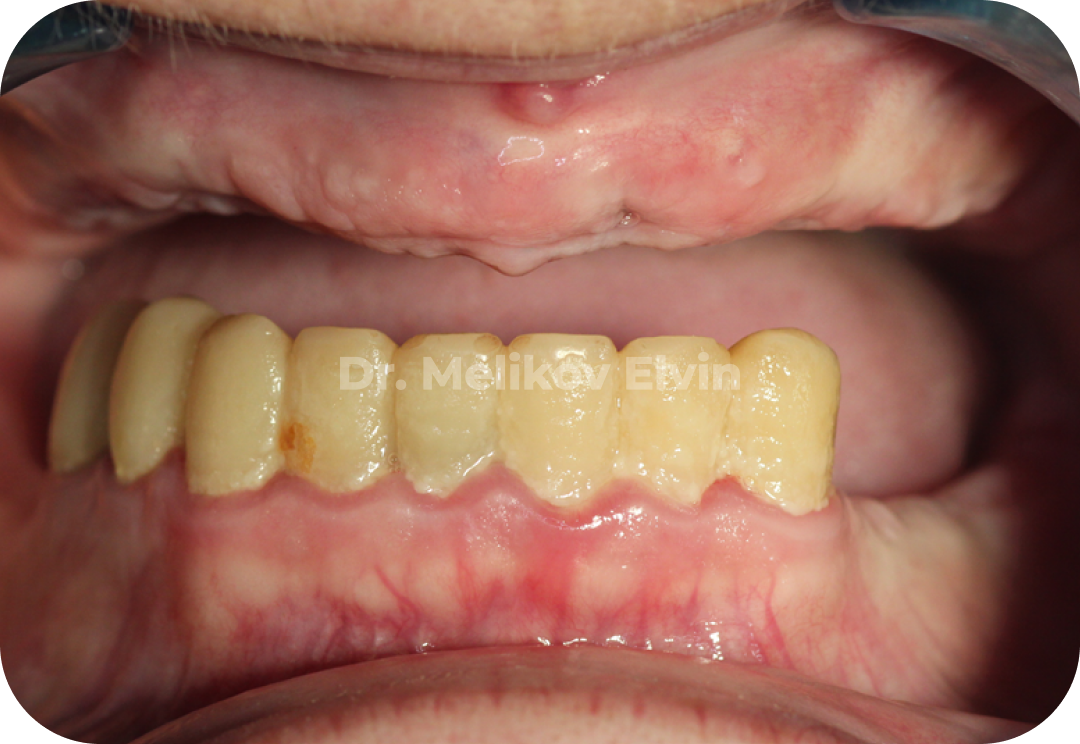

Ортопедические коронки на винтовой фиксации для нижней челюсти.

Фотографии после полной реабилитации.